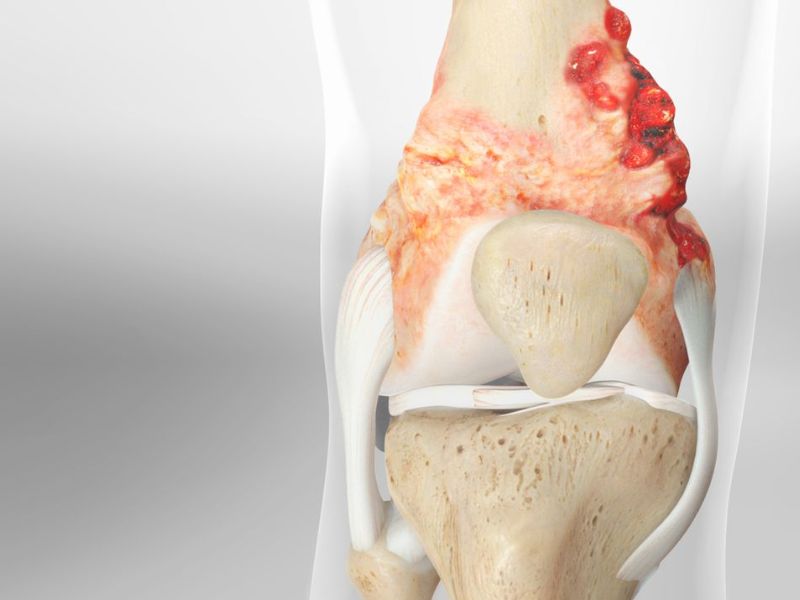

2.3. U tế bào khổng lồ

U tế bào khổng lồ, hay còn gọi là u đại bào, u hủy cốt bào là một dạng u lành tính nhưng có nguy cơ tiến triển thành ác tính nếu không được điều trị. Loại u xương này thường gặp ở đầu xương dài như xương chày, xương đùi và xương quay.